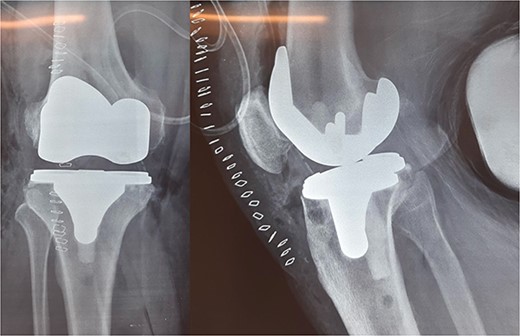

The patient underwent a medial-pivot design TKA (Evolution Medial-Pivot Knee System, Microport, China). Intraoperatively, a full ROM was achieved only after extensive soft tissue and bone releases. The extension gap was limited by significant hamstring spasticity, and a proper extension gap was attained after additional anterior femoral cut. Early postoperative recovery was uneventful (Fig. 2). On the third postoperative day, the patient complained of severe knee pain accompanied by excessive swelling during kinesiotherapy. Clinical examination showed a posterior sag sign at 30° of flexion (Fig. 3). No signs of neurovascular deficit were obvious. A knee X-ray revealed posterior TKA dislocation and a small, non-displaced femoral fracture (Fig. 4). The tibial component was reducible, but redislocation occurred with the knee extended over 90°, indicative of severe instability. Laboratory investigations, including erythrocyte sedimentation rate and C-reactive protein, were normal. A knee arthrocentesis was performed with no substantial findings. Two botulinum toxin injections (200 IU) to the hamstrings were performed without improvement. Local muscle hypertonia was evaluated through a neurological examination and a brain computed tomography scan, with no remarkable findings. The patient’s history included intramedullary nailing of the right femur due to an intertrochanteric fracture 8 months before the TKA.

The patient was reoperated, where a more extensive release of the hamstrings was performed, obtaining full extension. The knee was stabilized using a lateral external fixator (Fig. 5). Muscle biopsies were obtained, indicating signs of chronic inflammation. Full weight bearing, using a walker, was permitted from the first postoperative day without substantial complaints.